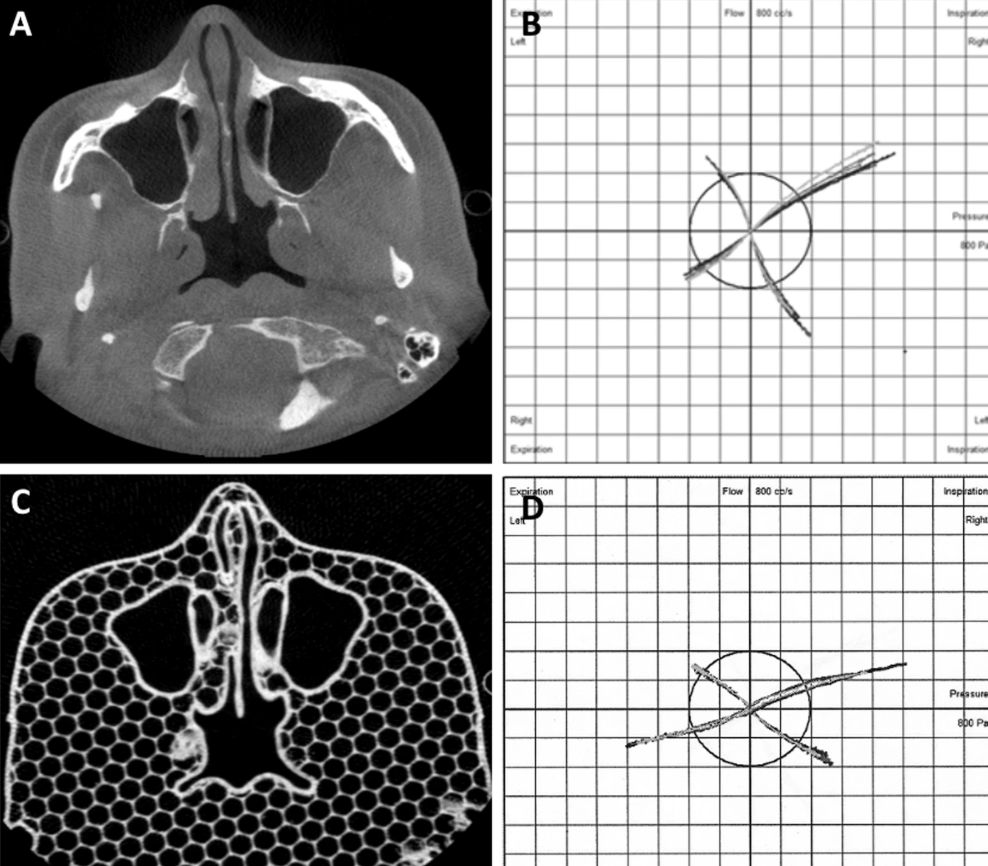

Finally, compare the airflow resistance of the printed part with the airflow resistance of the patient’s nose. This is done by using an instrument called a nasal pressure gauge, which is made specifically for this purpose. Using it on a patient is simple, but the printed part requires a certain DIY skill, so the researchers connected the tube to the back of the printed part and clipped the other end to the nose for scientific research.The resistance values of the two groups were similar, and the research team concluded that what they could not see before3D printingThe nasal passage method shows great promise for clinical application.

The patient’s CBCT scan and the corresponding PLA nasal pressure measurement model. The picture comes from the University of Tampere.